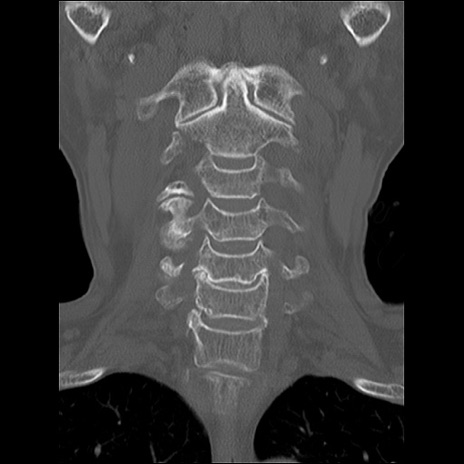

症例48 頚椎CT(冠状断像)

頚椎CT